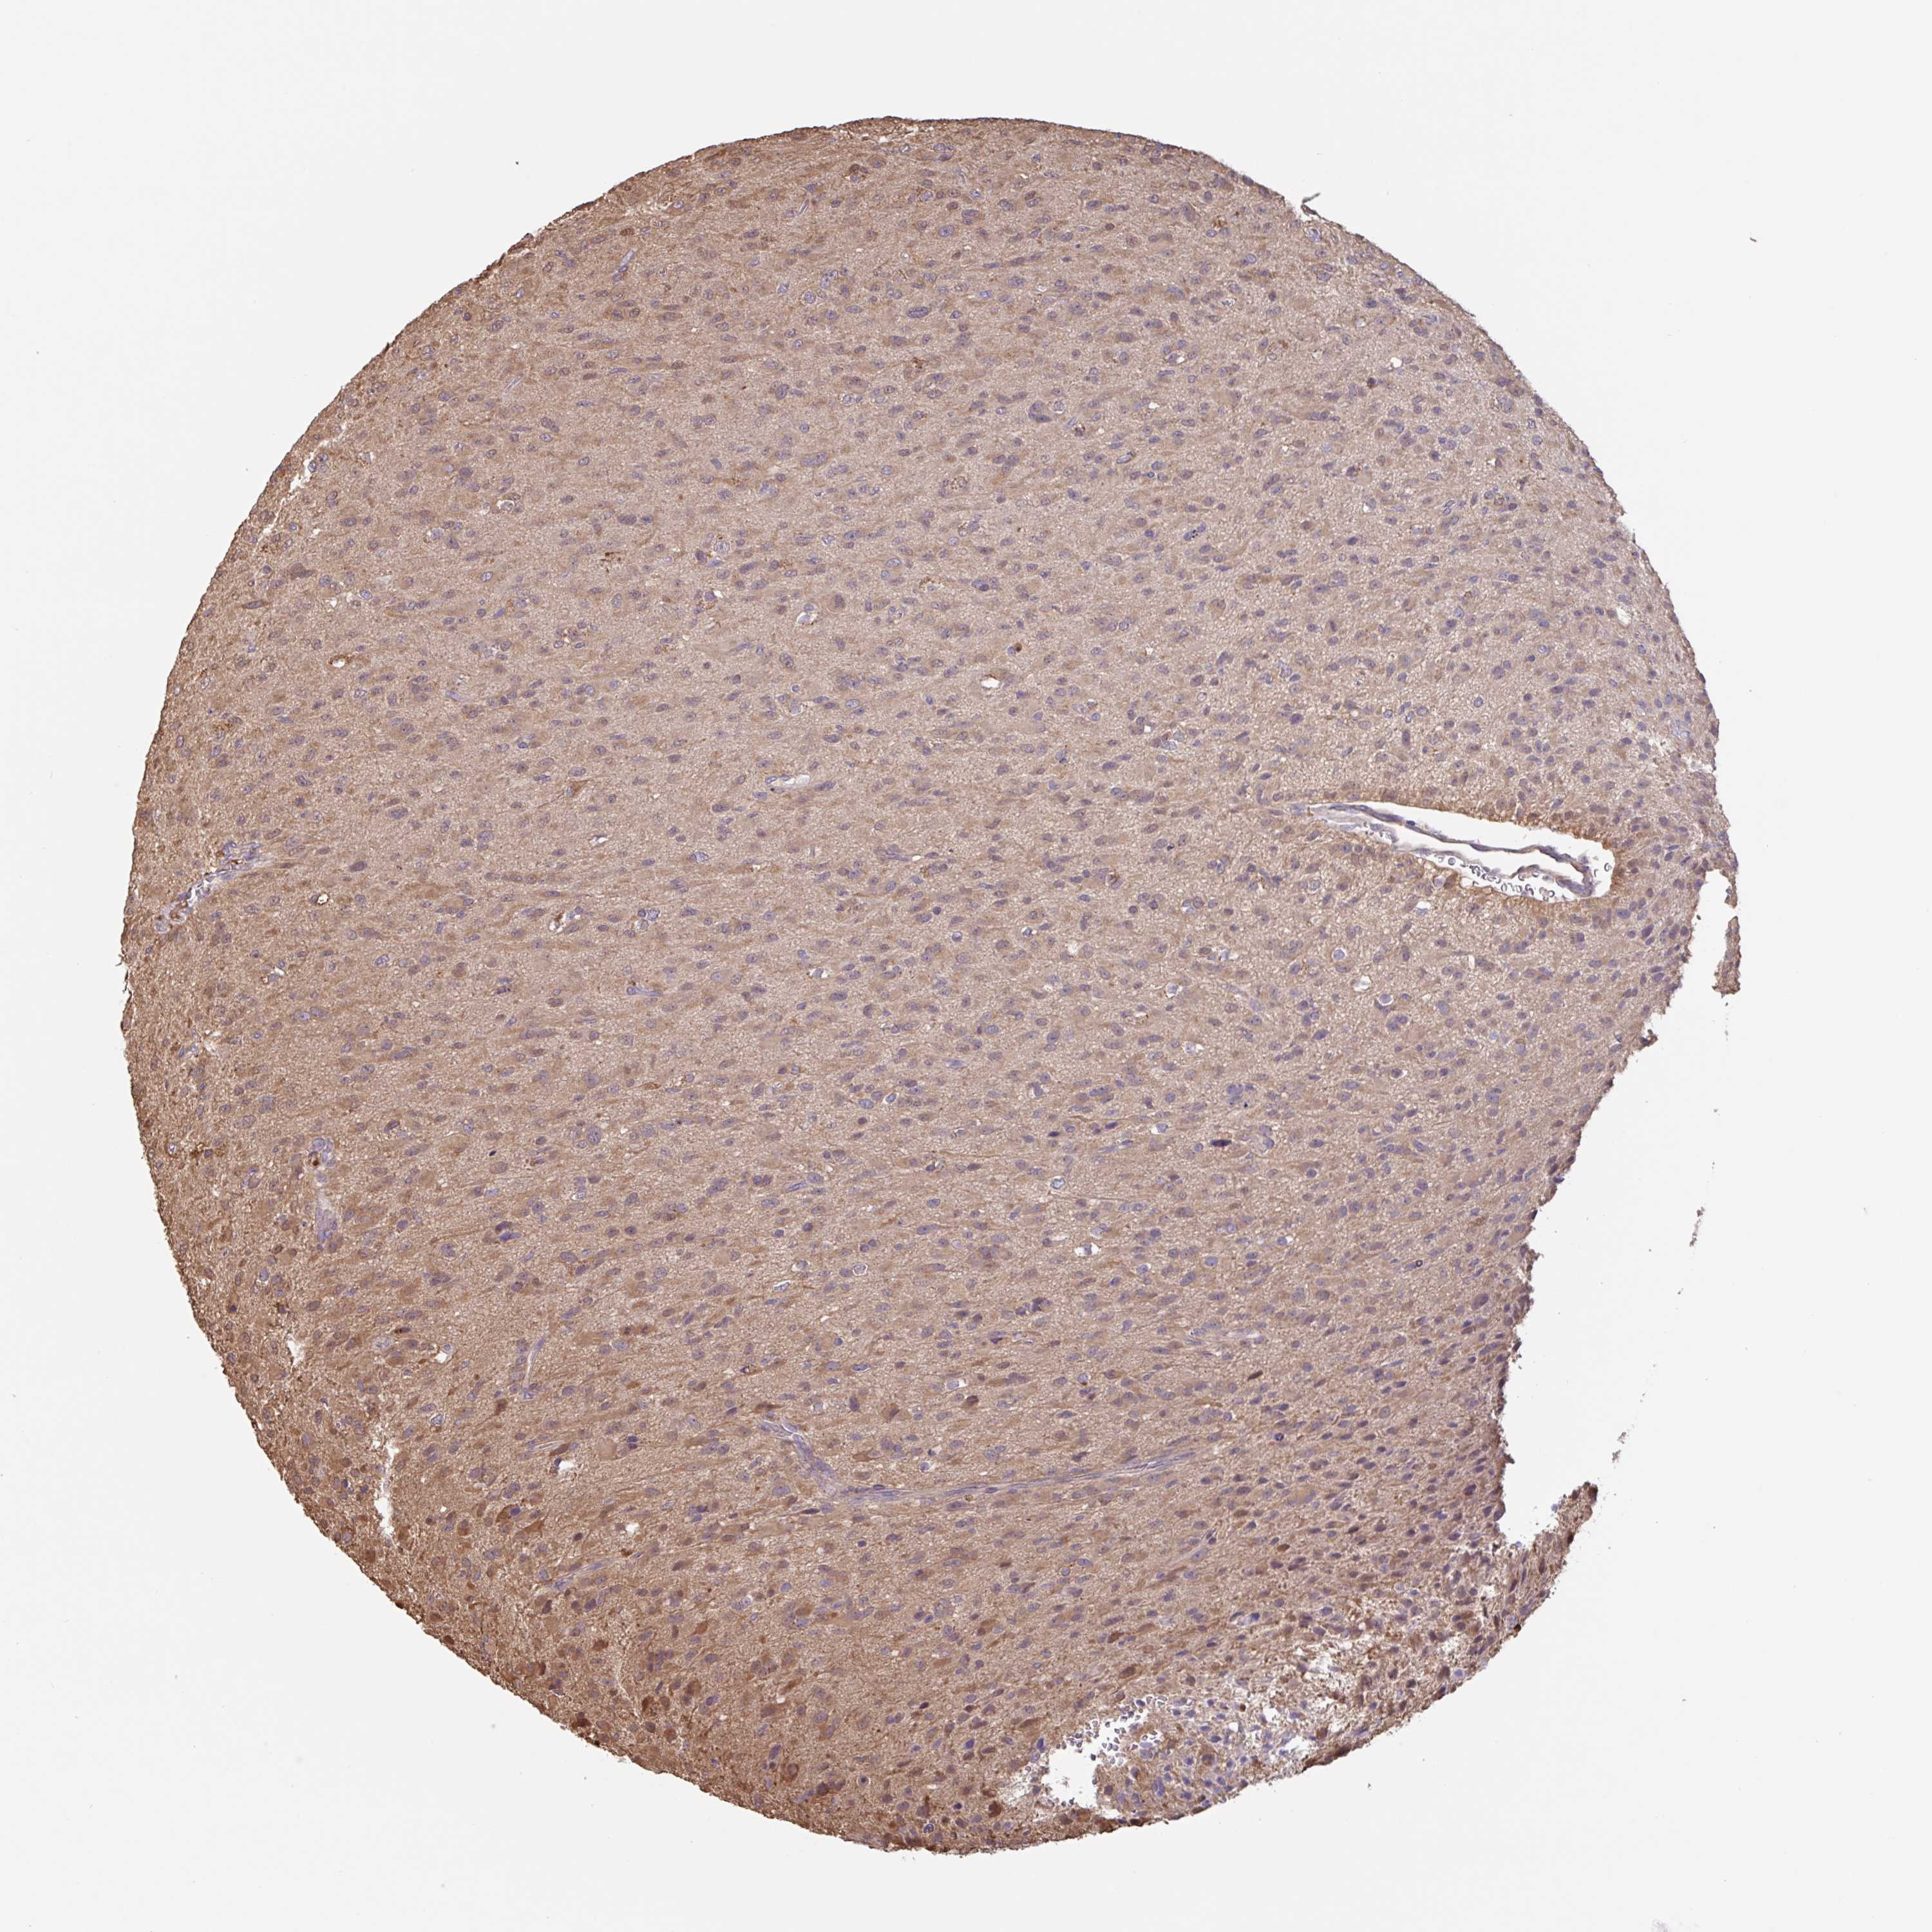

GLIOMA - Protein expressioni

A mouse-over function shows sample information and annotation data. Click on an image to view it in a full screen mode. Samples can be filtered based on level of antibody staining by selecting one or several of the following categories: high, medium, low and not detected. The assay and annotation is described here.

Note that samples used for immunohistochemistry by the Human Protein Atlas do not correspond to samples in the TCGA dataset.

Antibody stainingi

Antibody staining in the annotated cell types in the current human tissue is reported as not detected, low, medium, or high, based on conventional immunohistochemistry profiling in selected tissues. This score is based on the combination of the staining intensity and fraction of stained cells.

Each image is clickable and will lead to virtual microscopy that enables deeper exploration of all samples and also displays staining intensity scores, fraction scores and subcellular localization as well as patient and tissue information for each sample.

Antibody HPA024524

Antibody HPA053090

Staining

High

Medium

Low

Not detected

Intensity

Strong

Moderate

Weak

Negative

Quantity

>75%

75%-25%

<25%

None

Location

Nuclear

Cytoplasmic/membranous

Cytoplasmic/membranous,nuclear

Glioma, malignant, High grade

Glioma, malignant, Low grade